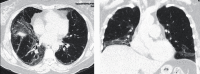

Interstitial lung disease (ILD) associated with connective tissue diseases (CTDs) is highly heterogeneous in its clinical presentation and course. The diagnosis and management of CTD-ILD require a multidisciplinary approach involving, at minimum, a rheumatologist, a pulmonologist, and a radiologist. Close monitoring of patients with CTD-ILD is important to enable early detection of disease progression and inform decisions regarding the initiation or escalation of pharmacotherapy. In the absence of guidelines regarding how CTD-ILDs should be treated, clinicians face difficult decisions on when to use immunosuppressant and anti-fibrotic therapies. The importance of a multidisciplinary and individualized approach to the diagnosis and management of CTD-ILD is highlighted in the three case studies that we describe in this article.